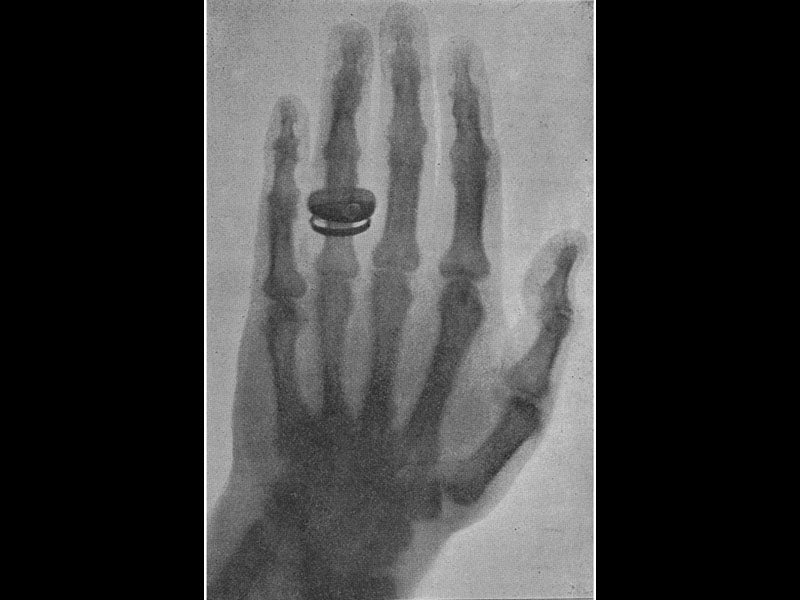

Wilhelm Röntgen, a German physicist, died Feb. 10, 1923, at age 77. Röntgen taught at German universities at Strassburg (recently annexed) and Giessen before settling into the desirable chair of physics at Würzburg. It was there, in the fall of 1895, that Röntgen made the discovery that ensured his fame. On Nov. 8, 1895, Röntgen was investigating spurious radiation produced by various cathode ray tubes when subjected to high voltages. He noticed that even when the tubes were covered by black cardboard, radiation from the tubes was able to make a phosphorescent screen across the room glow in the dark. Some kind of radiation was passing right through the supposedly opaque cardboard. He called the mysterious radiation "X-rays,” and he investigated their properties extensively for the next six weeks. On Dec. 22, 1895, he took a photograph of his wife's hand that showed every bone within, as well as a now seemingly oversized wedding ring (first image above), and the import of his discovery set in.

He published his first paper on the phenomenon, "Über eine neue Art von Strahlen" (“On a new kind of radiation”) before the year was out, and within a few weeks, X-rays were a world-wide phenomenon. Everyone except Röntgen called them Röntgen rays. His discovery effectively launched what is sometimes called the Second Scientific Revolution, as, in short order, physicists in France and England discovered: radioactivity (1896), the electron (1897), radium (1898), alpha and beta radiation (1899), and gamma rays (1900). For his discovery, Röntgen received the very first Nobel Prize in Physics in 1901. We have all three of his seminal papers in our serials collection, and we displayed one, showing a print of an X-ray photograph of yet another hand-with-ring, in our 2010 exhibition, The Atomic Age (third image).